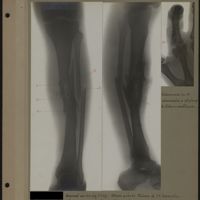

0100 - Page 96 - [Radiographies du tibia et de la fibula]0100 - Page 96 - [Radiographies du tibia et de la fibula]